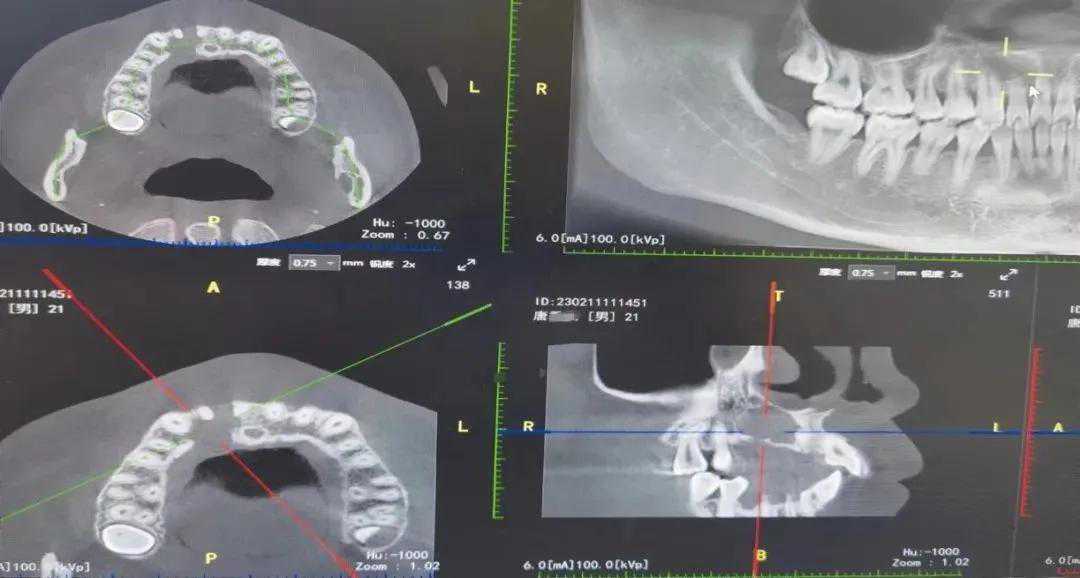

为切实缓解“看病远”问题,拜城县各医共体单位成立了专家流动手术团队,根据患者需求,随时下乡开展手术。同时,通过远程医疗及远程影像、远程心电、远程病理等,指导乡镇卫生院和村卫生室开展医疗服务。

1月至2月,拜城县开展远程会诊108例,较2020年同期增长20.4%;远程心电409例,较2020年同期增长88.4%。“花卫生院级别的钱享受县级医疗服务,好多病在乡里也能治好啦。”患者怕提古丽·亚森说。